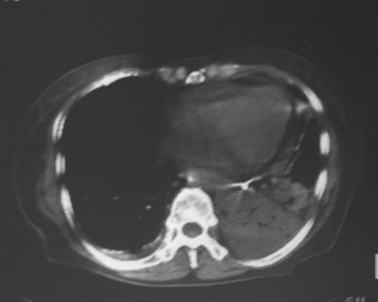

女,80岁,10天前胸片示双下肺感染,正规治疗后复查。体温不高,有脓痰,无臭味。

左肺下叶大部实变,内可见含气支气管征。后部见长椭圆形低密度区,周围坏一薄壁。

考虑:左下肺炎症,包裹性胸腔积液。

支持:左肺下叶大部实变,内可见含气支气管征。后部见长椭圆形低密度区,周围环一薄壁,局部胸膜增厚。结合病史考虑:左下肺炎症,包裹性胸腔积液。

左肺下叶炎症并脓肿形成,双侧胸膜炎

左下肺脓肿伴左下胸腔包裹性积液。